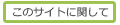

有鈎骨(手) (ゆうこうこつ、英:hamate)

・有頭骨は手根骨の1つで、遠位手根骨の中で最も内側(小指側)に位置する。